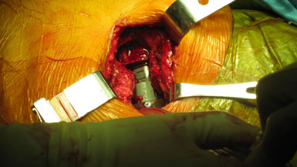

| Femoral canal preparation is begun with an opening into the femur with a starting awl, followed by a circular box chisel. |

| Distal canal reamers encounter a bony bridge which was anticipated so intra-operative decision confirmed pre-operative plan to shorten the stem implant length. |

| Apex Modular Stem was used that features a special “Dual Press” modular junction. This design allows for selection of a variety of femoral offsets and one of three version angles: Neutral or 13º of anteversion or retroversion. |

| Pre-operative consideration was discussed on shorting the stem to avoid any potential femoral canal perforations. For this reason a special proximal modular stem “Dual-Press” design was utilized. Proximal conical reaming was done without the use of a pilot shaft along with rasping of the femoral triangle. |

Careful intra-operative measurements were done then surgery on the stem to customize “shortening of the stem” stem length. |

The Midas Rex® power system was used to cut the distal portion of the stem off.

| The stem fit was excellent with impressive implant to bone stability. The proximal modular neck design allowed selection of a variety of femoral offsets and neck lengths. This along with large head M-O-M (40mm) bearings provided significant ROM and hip joint stability. The short stem functions as a pilot with implant to bone stability provided by proximal stem geometry (cone & triangle). |

Modular necks allows for neutral or 13º of anteversion or retroversion. In this case the head-neck was retroverted for best joint stability position. Target Restoration was established. |

| You will notice when you take out the pelvic obliquity it is 45 degrees |

Before surgery he stated he had constant pain especially in his back. After his fusion takedown his back pain has been completely resolved. Patient was up on his own day 1 and discharged on day 2.